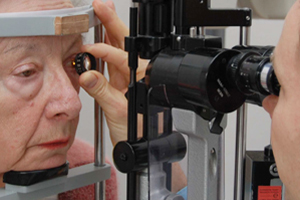

Zum einen kann der Augeninnendruck mit einem sogenannten Applanationstonometer bestimmt werden. Tut nicht weh – das Auge wird betäubt. Nach Anfärbung der Hornhaut wird durch Auflegen eines kleinen Druckkopfes auf das Auge der Augeninnendruck ermittelt.

Applanationstonometer

Die Spaltlampenuntersuchung ist eine der wichtigsten Augenuntersuchung und wird gewöhnlich bei jedem Augenarztbesuch durchgeführt. Es handelt sich um ein spezielles Mikroskop, welches dem Arzt einen Überblick über die Details des vorderen Augenabschnittes liefert. Zum einen stellt die Spaltlampe das Auge stark vergrößert dar, zum anderen erlaubt das durch die Pupille projizierte, schmale konzentrierte Lichtbündel einen Einblick quer durch das Auge. Damit können die Strukturen und Gewebe sowie eventuelle Trübungen oder andere krankhafte Veränderungen erkannt werden.

Die Spaltlampenuntersuchung ist einfach und schnell durchführbar. Sie wird für die Diagnostik verschiedener Augenerkrankungen (Bindehautentzündung, Grauer Star, Keratokonus, Iritis - um nur einige wenige zu nennen) verwendet. Da die Hornhaut und die Augenlinse im Normalfall durchsichtig sind, ist es auch möglich, mit Hilfe einer speziellen Lupe den Augenhintergrund an der Spaltlampe zu betrachten.

Spaltlampenuntersuchung

Augenhintergrundbetrachtung mit spezieller Lupe

Mikroskopie des vorderen Auges